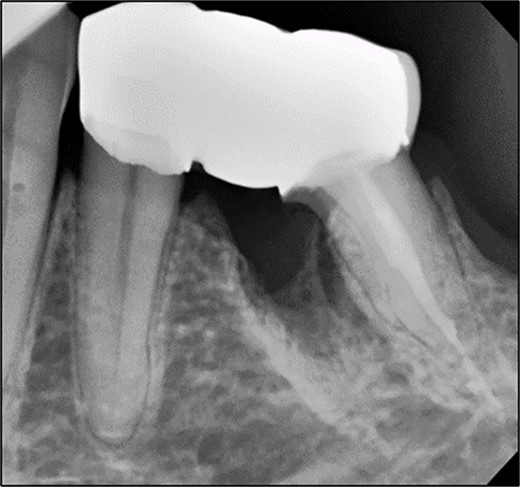

A 44-year-old patient presented to our clinic with the primary complaint of food lodgment in a cavity on the lower left posterior teeth. Clinical examination revealed extensive caries on the disto-occlusal surface of the lower left first permanent molar (tooth 36) (Fig. 1). Radiographic examination showed a large radiolucency at the distal crown extending to the cervical third of the distal root, with periapical radiolucencies on both mesial and distal roots (Fig. 2). The tooth was diagnosed with asymptomatic irreversible pulpitis and symptomatic apical periodontitis.

Periapical radiograph of tooth 36 showing a large radiolucency area at the distal crown involving the cervical third of the distal root.